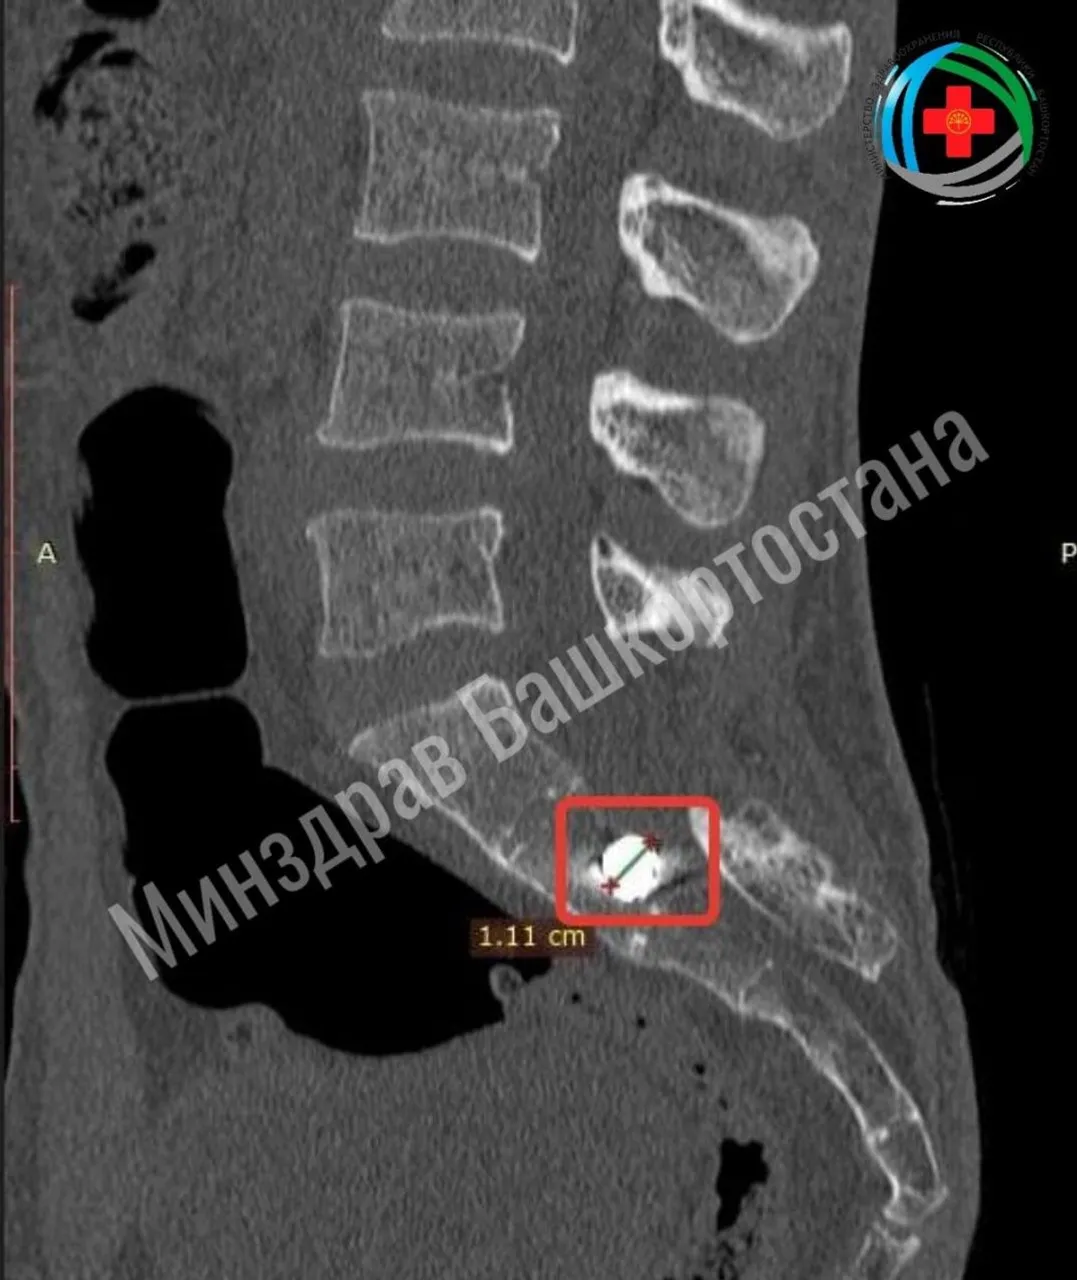

При обследовании врачи обнаружили осколочное ранение крестца с инородным телом. Осколок вошел в область ребер справа, прошел через мягкие ткани, повредив поперечный отросток пятого поясничного позвонка и раздробив задние отделы крестца. Он также пробил спинной мозг и застрял в кости.

Нейрохирурги успешно удалили инородное тело — осколок кубической формы размером 1 см. Операция прошла без осложнений: врачи аккуратно обошли спинной мозг, не повредив его.